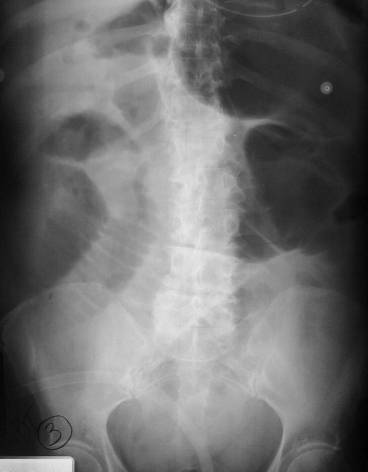

Cecal Volvulus

Dilated loop in LUQ is cecum which has twisted on itself

Dilated loops of small bowel from small bowel obstruction at ileocecal valve